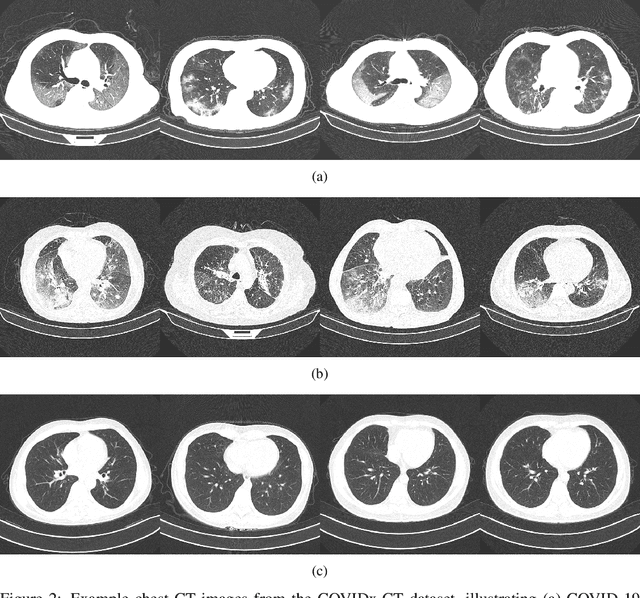

Abstract:The coronavirus disease 2019 (COVID-19) pandemic continues to have a tremendous impact on patients and healthcare systems around the world. In the fight against this novel disease, there is a pressing need for rapid and effective screening tools to identify patients infected with COVID-19, and to this end CT imaging has been proposed as one of the key screening methods which may be used as a complement to RT-PCR testing, particularly in situations where patients undergo routine CT scans for non-COVID-19 related reasons, patients with worsening respiratory status or developing complications that require expedited care, and patients suspected to be COVID-19-positive but have negative RT-PCR test results. Motivated by this, in this study we introduce COVIDNet-CT, a deep convolutional neural network architecture that is tailored for detection of COVID-19 cases from chest CT images via a machine-driven design exploration approach. Additionally, we introduce COVIDx-CT, a benchmark CT image dataset derived from CT imaging data collected by the China National Center for Bioinformation comprising 104,009 images across 1,489 patient cases. Furthermore, in the interest of reliability and transparency, we leverage an explainability-driven performance validation strategy to investigate the decision-making behaviour of COVIDNet-CT, and in doing so ensure that COVIDNet-CT makes predictions based on relevant indicators in CT images. Both COVIDNet-CT and the COVIDx-CT dataset are available to the general public in an open-source and open access manner as part of the COVID-Net initiative. While COVIDNet-CT is not yet a production-ready screening solution, we hope that releasing the model and dataset will encourage researchers, clinicians, and citizen data scientists alike to leverage and build upon them.